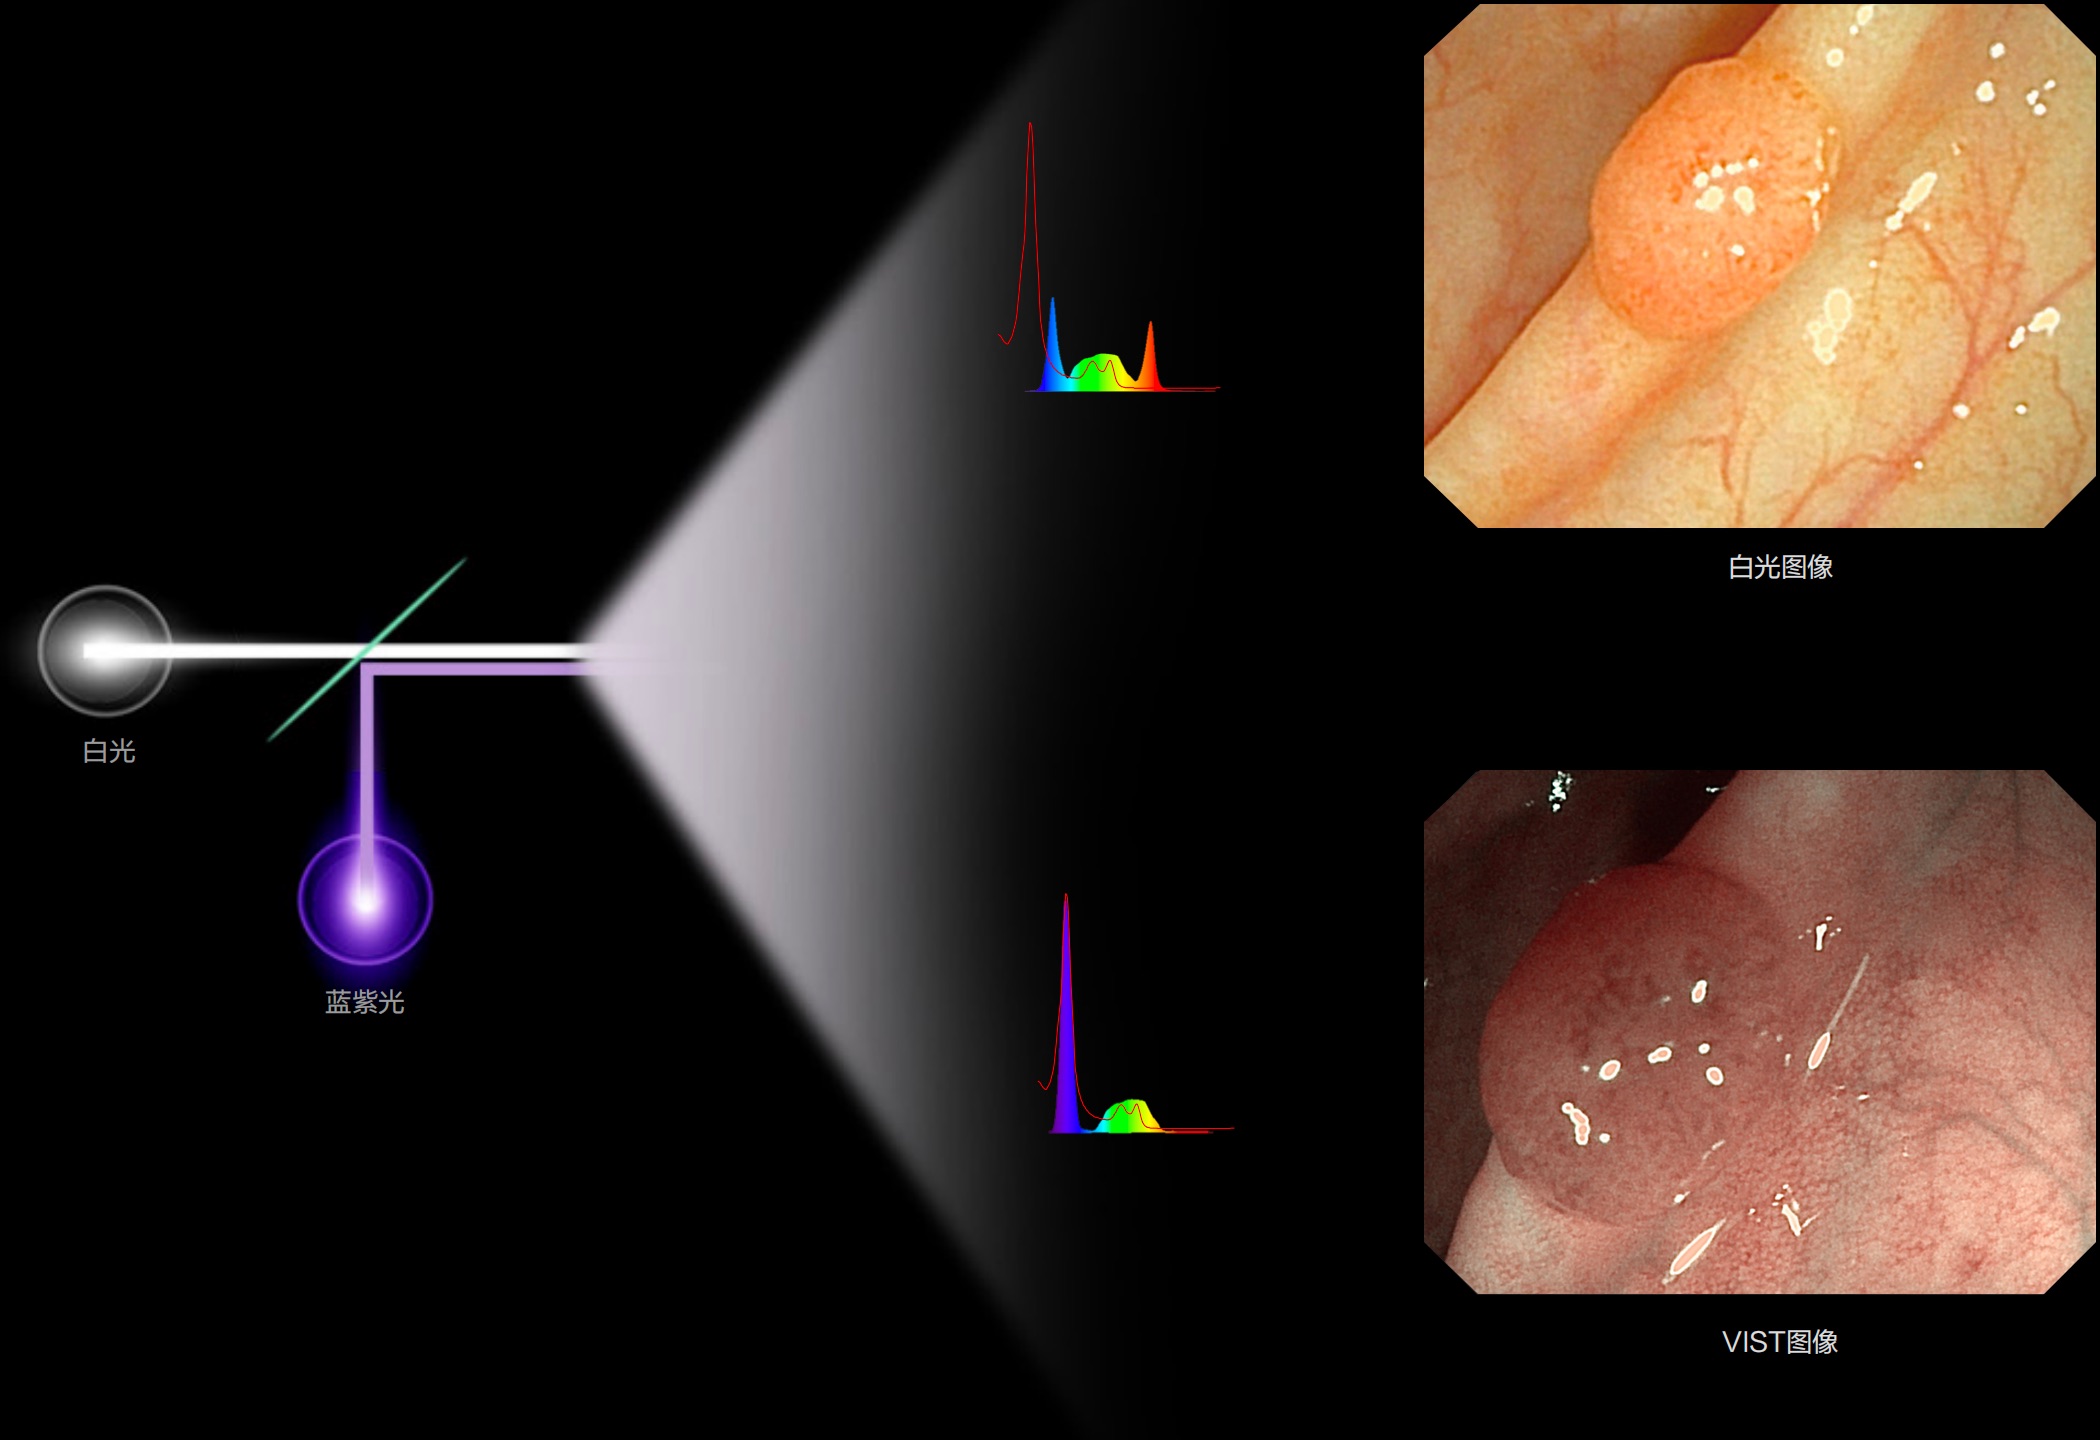

(Spectral Focused lmaging, SFI)

能够凸显黏膜浅层和中层血管轮廓,适用于中、远景观察下的病灶识别和早癌筛查。

(Versatile Intelligent Staining Technology)

能够凸显黏膜浅层血管轮廓和黏膜表面微结构,适用于中、近景观察下的早癌精确诊断。

白光图像

SFI图像